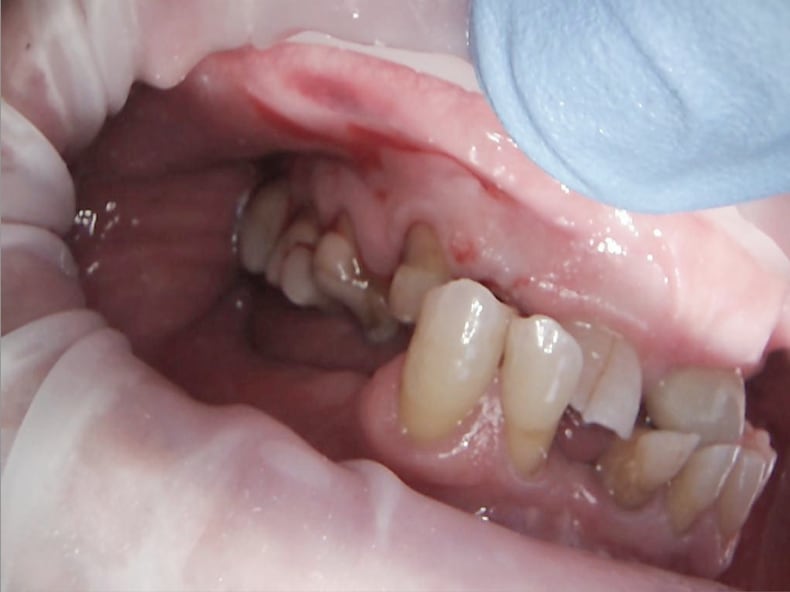

Anecdote : patiente 28 ans qui arrive en pleurs chez moi.

Il manque 6 dents dont une 22.

Elle est caissière dans une grande surface ( à temps partiel ) et gagne 850 euros par mois. Seule avec 2 gosses.

Elle s'est faite engeuler par son chef parce qu'il lui manque la 22 et en caisse ça la fout mal , au niveau présentation.

Le confrère lui propose 6 implants + ceram : devis 15 000 €.

Docteur : je ne peux pas ...

Réponse du confrère : vous n'avez qu'à faire un crédit. Véridique !!!

A cette patiente j'ai fait une dent provisoire et un bridge pour sa 22 .( paiement en 4 chèques ).

Les 5 autres dents sont toujours absentes.

Et 21 -23 étaient saines?

A savoir si 21 23 étaient saines ?

OUI .

Il existe un truc qui s'appelle le bridge collé.

Et même dans ma campagne, loin des grandes villes, il arrive que j'en fasse.